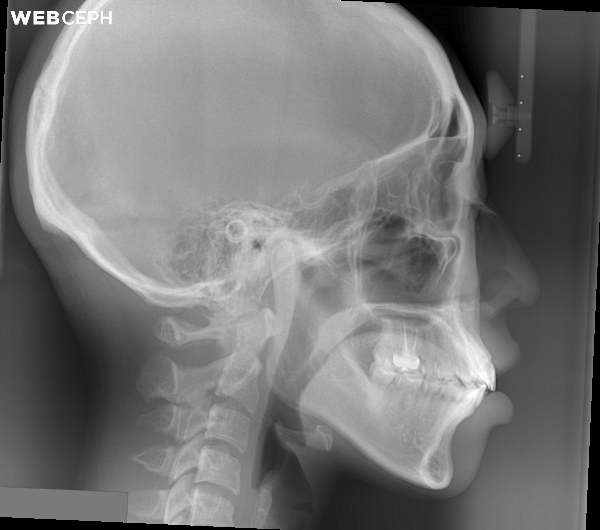

很多人牙齒不亂但是嘴唇無法閉合,除了暴牙之外也有時伴隨著上下齒列過度萌發,垂直高度過多,此時必需同時後退前牙也必須上壓齒列 而這個多半需要做精準的骨釘力學控制,才能完全將嘴唇閉合達到一個自然的側面外觀~